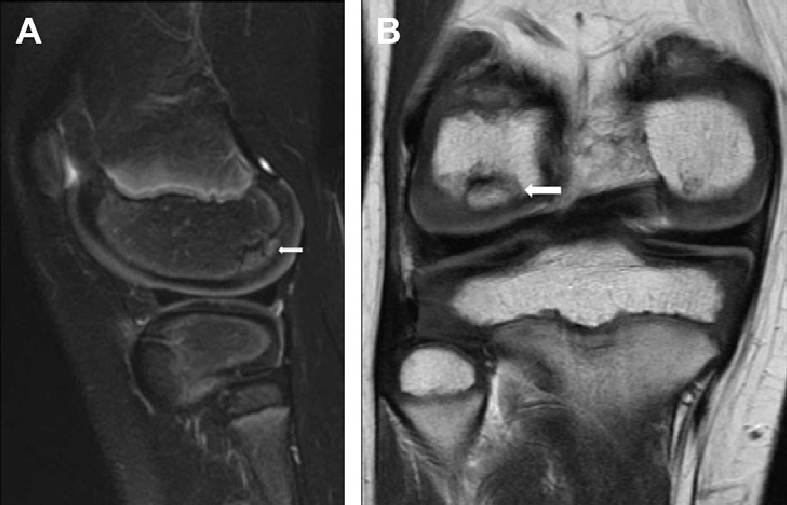

Osteochondritis dissecans (OCD) is a joint condition that occurs when a piece of bone and its overlying cartilage become loose due to a lack of blood supply. This can lead to pain, swelling, and potential joint instability, particularly in the knee. OCD commonly affects adolescents and young adults, often as a result of repetitive stress or minor trauma to the joint. Understanding the causes, symptoms, and treatment options for OCD is essential for managing the condition and preserving joint health.

OCD is a condition in which a portion of the bone beneath the cartilage in a joint loses its blood supply, leading to the separation of bone and cartilage. In some cases, the loose fragment may remain attached, while in others, it can break free and move within the joint, causing mechanical symptoms. OCD most commonly affects the knee, particularly the femoral condyles (the rounded ends of the thighbone), but it can also occur in other joints such as the elbow and ankle.